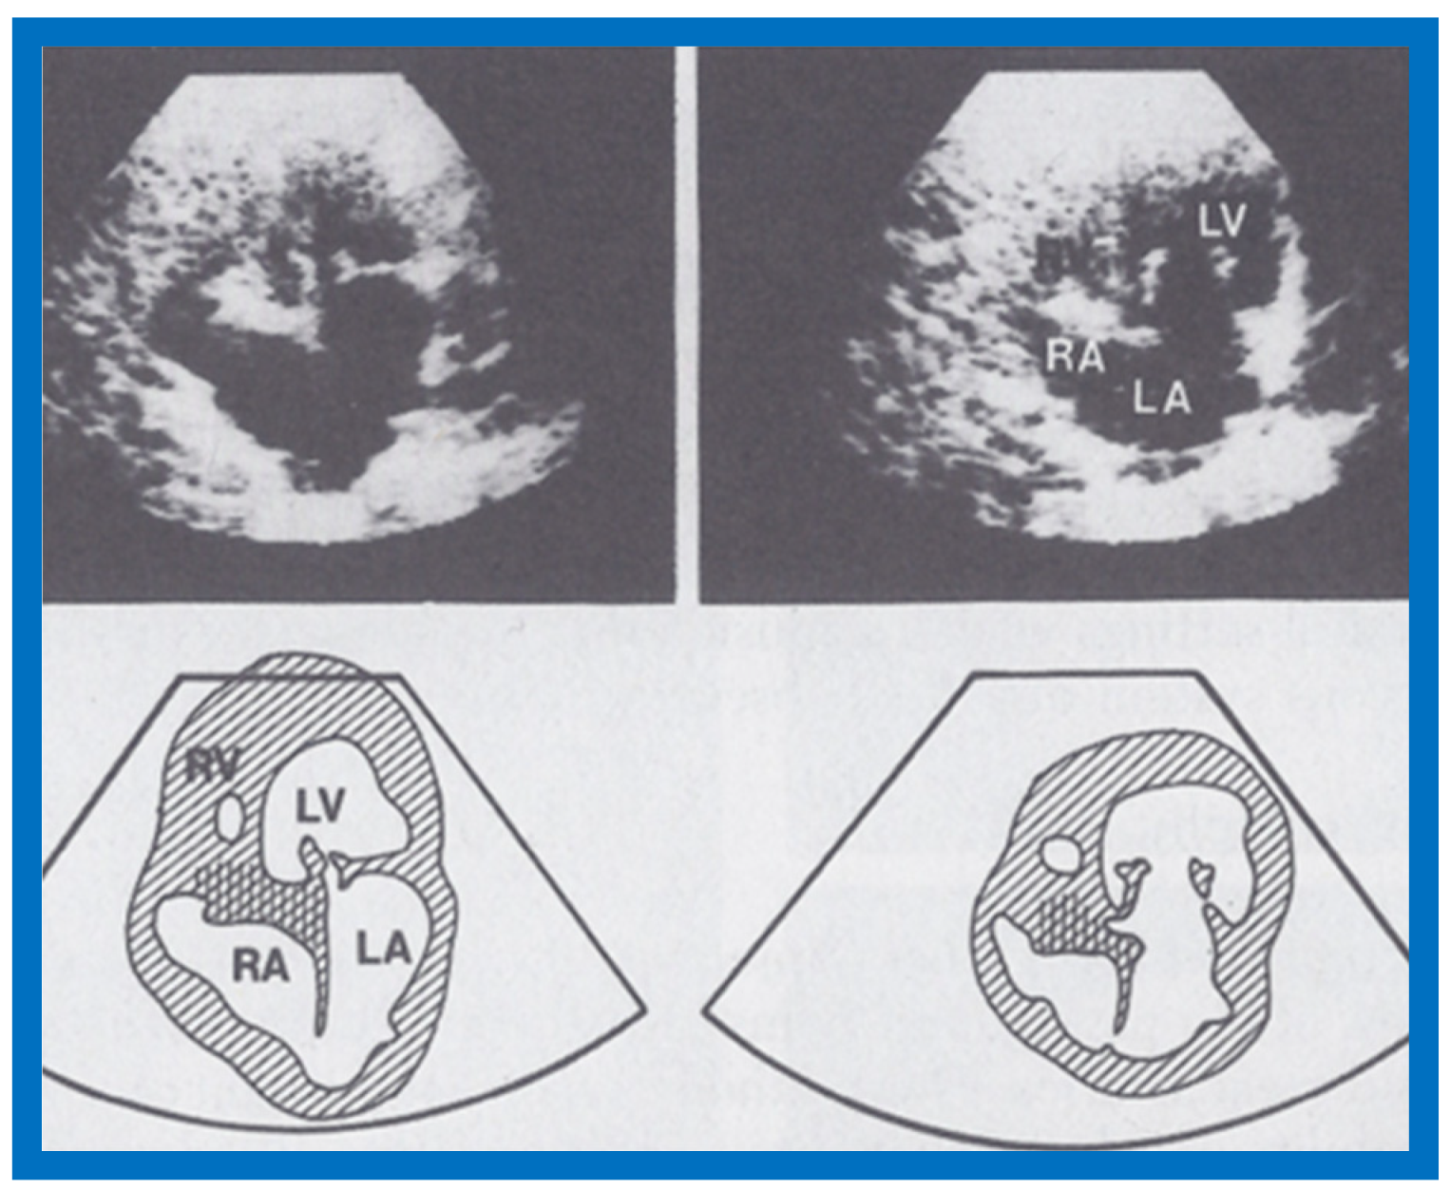

The M-mode and two-dimensional echocardiographic features of tricuspid atresia were discussed in the author’s first book on tricuspid atresia, written in collaboration with his colleague, Dr Wesley Covitz at the Medical College of Georgia [7]. The two-dimensional (2D) echocardiographic pictures in 1982 were crude (Figure 14) [7]; however, they represented the state of the art echocardiography machines of that time.

Figure 14.

Selected video frames from apical four-chamber view of a two-dimensional (2-D) echocardiographic study demonstrating dense band of echoes between the right atrium (RA) and hypoplastic right ventricle (RV). Line drawings are shown beneath the 2D frames. Note that the mitral valve is closed in the left image while it is open in the right image. The atretic tricuspid valve echoes remain unchanged. LA, left atrium; LV, left ventricle. Reproduced from Covitz W., Rao P.S. [7].

More recently, the author reviewed the echo-Doppler evaluation of tricuspid atresia [37,38,39]; these findings will be presented. M-mode echocardiography, while not diagnostic, is useful for evaluating the size of the left atrium (LA) and left ventricle (LV) and LV function. On 2D echocardiography, the atretic tricuspid valve is visualized directly as a dense band of echoes at the site where the tricuspid valve should be in the most frequent muscular type, as shown in Figure 14, Figure 15, Figure 16 and Figure 17. This anatomy is better demonstrated in apical and subcostal four-chamber views than in other views. The other types, namely membranous, valvular, Ebstein’s, atrioventricular septal and unguarded valve with muscular shelf (Figure 18) [40], are rare and may also be recognized on 2D echocardiography.